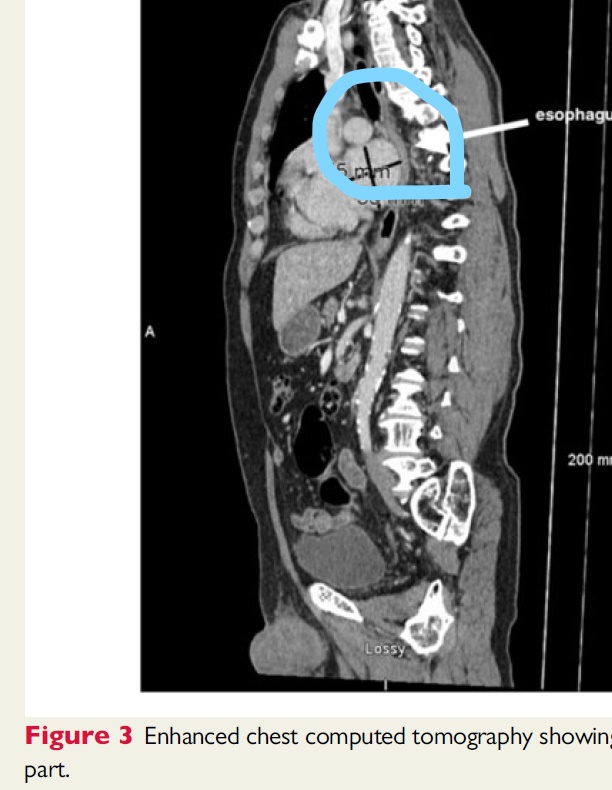

胸部造影CTは巨大な左心房が食道中部を後方へ移動させており、中部食道を圧迫していることを明らかにした。

胸部造影CTにおいて、前後径81mm,横径45mmの巨大な左心房が食道中部を後方に圧迫し移動させていることが明らかになった。(図3)